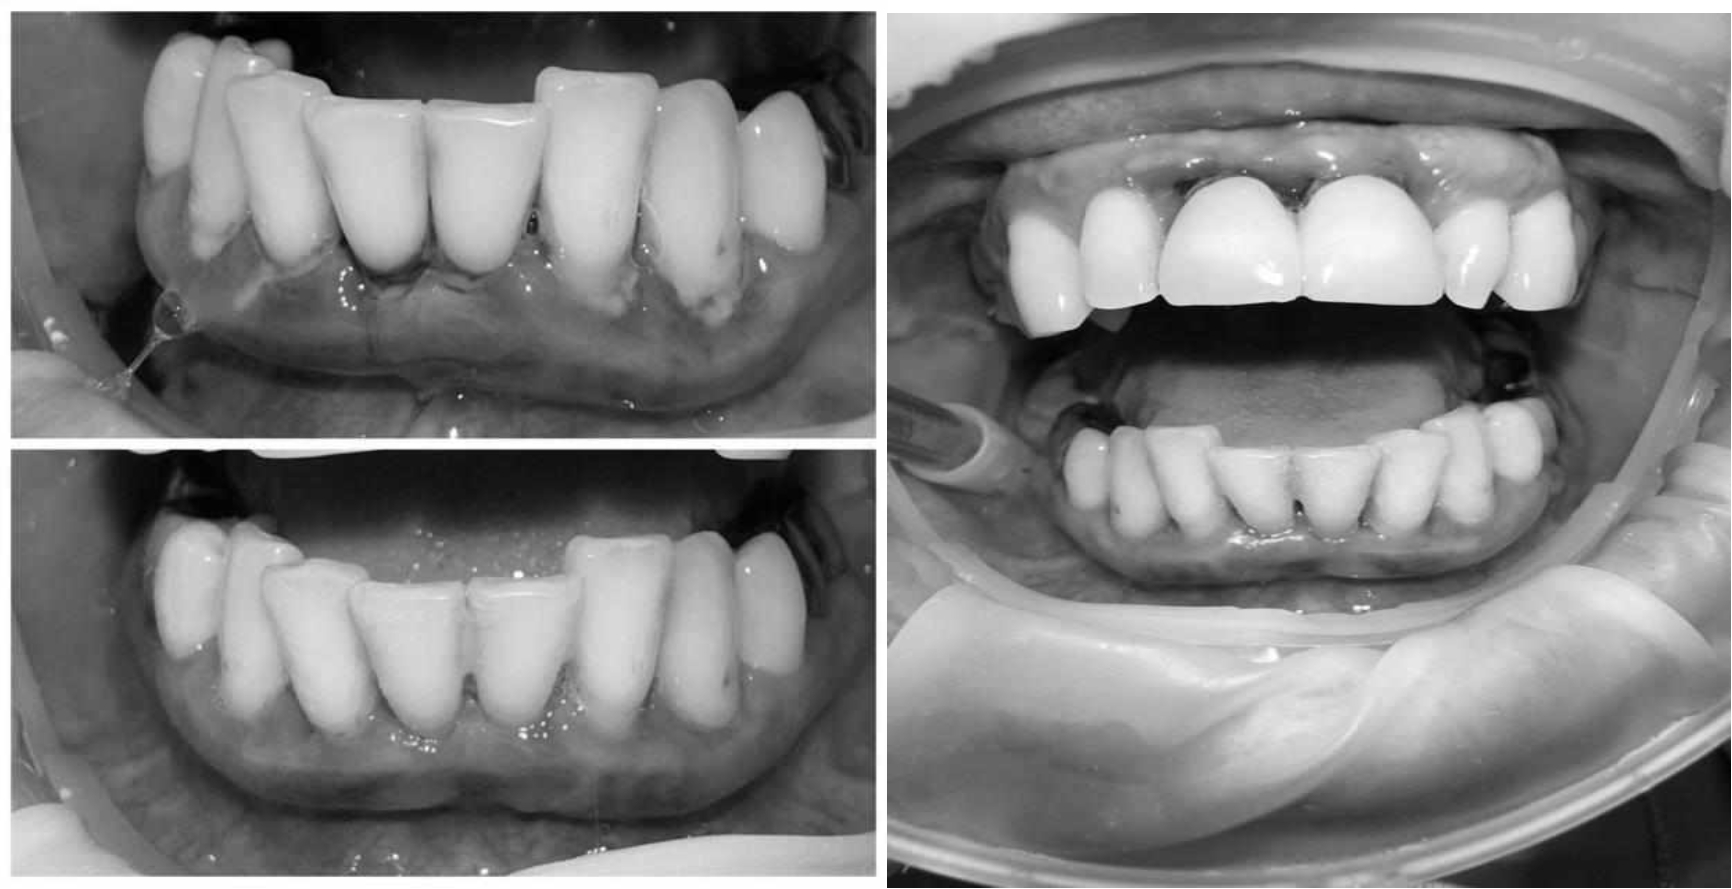

Ранее у пародонтолога не наблюдалась. При осмотре выявлены: неудовлетворительная индивидуальная гигиена полости рта, пародонтальные карманы до 7 мм, обильная кровоточивость и гноетечение из пародонтальных карманов, подвижность зубов 4.2, 4.1, 3.1, 3.2 II степени, обильные над- и поддесневые зубные отложения (рис. 1). На ортопантомограме отмечается резорбция костной ткани до ½ длины корня, очаги остеопороза (рис. 2). Пациенту был поставлен диагноз хронический генерализованный пародонтит тяжелой степени тяжести. При осмотре была составлена пародонтограмма с использованием компьютерного зондирования (рис. 3).

Рис. 2. Ортопантомограмма исходной ситуации пациента состояния полости рта

Через 6 месяцев при осмотре выявлен удовлетворительный уровень индивидуальной гигиены, отсутствие участков кровоточивости и гноетечения (рис. 4), пародонтальные карманы уменьшились в размерах (рис. 5). Пациент отмечает значительные улучшения. После стабилизации пародонтологического статуса пациент направлен для дальнейшего ортопедического лечения.

Рис. 4. Динамика результата через 6 месяцев